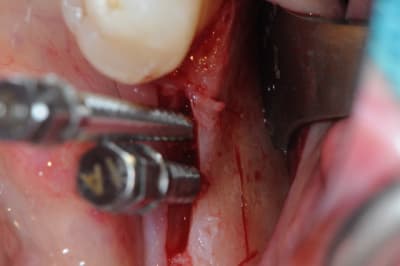

Cas 1-coté gauche maintenant:

1- ouverture, forme et configuration différente

2- une fois échauffée avec le coté droit, je me dis allez hop, j'attaque une expansion. donc incision crestale avec décharges osseuses

3- mise en place des expanseurs de Mesinger A et B

4-5 notez que l'incision de décharge étant oblique , elle sert également de garde fou contre une éventuelle fracture osseuse. l'os "mobile" vient buter contre l'os "immobile"

la suite en primeur pour ceux qui viennent à Sallanches les 28 et 29 Mars...

Bravo D57 pour ta chirurgie de reconstruction avec le systeme Fast.

mais j'ai quelques remarques:

1. tes vis ne sont pas positionnées comme il faut.

2. tes vis sont trop enfouies

3. tes sutures ne sont pas assez profondes. comme je te le disais à l'ADF, tu dois être à au moins 1 cm de la berge.

4. Donc, je peux te le dire d'avance: le résultat sera moyen. Je t'avais proposé de préparer ensemble le protocole chirrugical. dommmage.